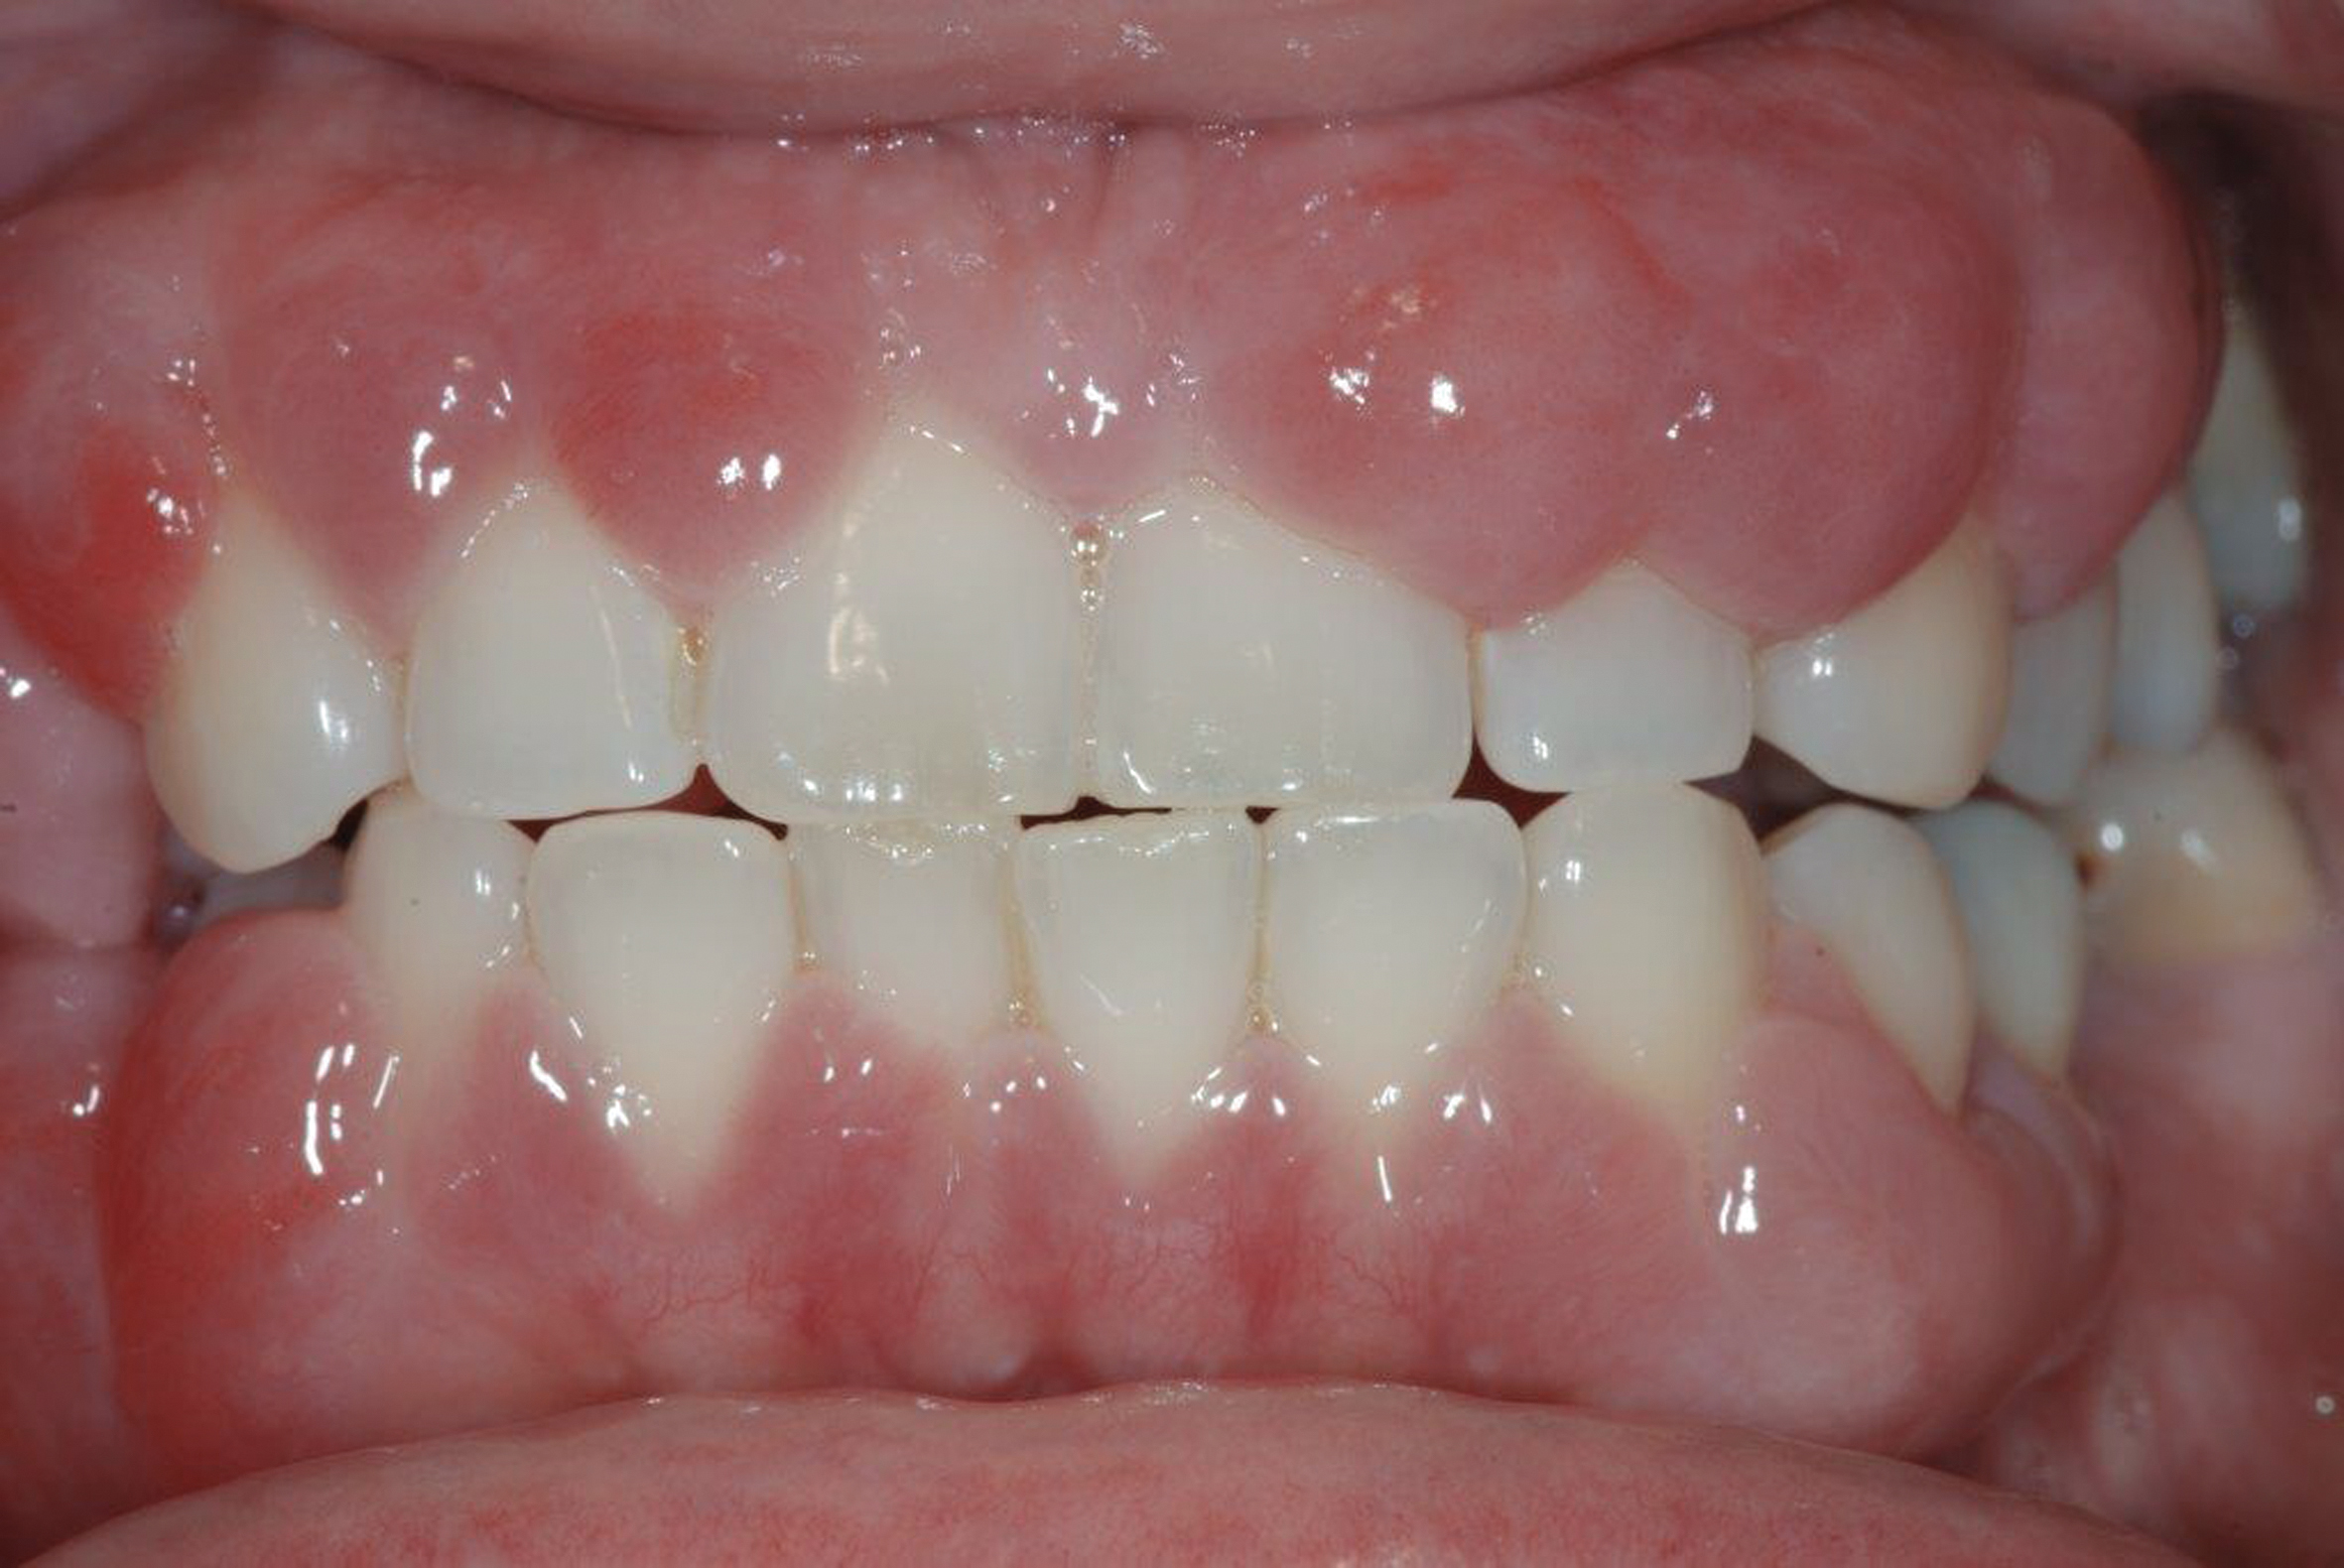

Smile line assessment is a validated process that is used for esthetic evaluation.1 Gummy smile (GS) has been defined as a nonpathological condition causing esthetic disharmony in which more than 3 mm of gingival tissue is exposed when smiling2 (Figure 1). The possible causes are excessive maxillary growth, short upper lip, or abnormal eruption of maxillary anterior teeth. Subsequently, short tooth syndrome (STS) has been defined as a condition caused either by excessive gingival display or lack of incisal tooth display during smiling or a low smile line.3

Fig 1. Patient with a gummy smile.

Figure 1